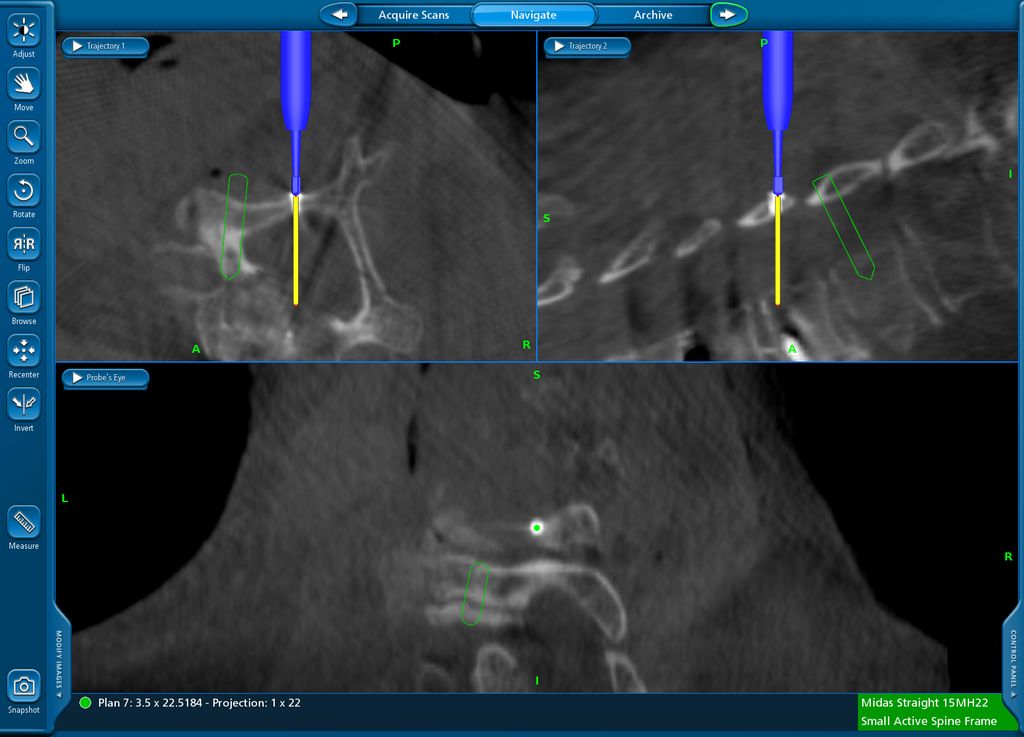

Intraoperative 3D-Visualisierung

Die Navigation stellt nicht nur beim Einbringen von Implantaten eine Hilfe dar, sondern kann auch in anatomisch herausfordernden Situationen rein zur Verbesserung der Orientierung zu Hilfe genommen werden. Mögliche Anwendungsfelder stellen hier beispielsweise die untere HWS oder der zervikothorakale Übergang dar, welche im konventionellen Röntgen teilweise schwer darstellbar sind. Abbildung 16 zeigt den MR-Befund einer 32-jährigen Patientin, die auswärtig zur ACDF C6/7 indiziert wurde, wobei der Eingriff dort aber aufgrund der Unmöglichkeit, die HWS unter Durchleuchtung entsprechend einzustellen, nicht erfolgte. Abbildung 17 zeigt das intraoperative Röntgen mit bereits kräftigem Schulterzug, in dem aber nur mehr das Segment C4/5 sicher beurteilt werden kann. In diesem Fall erfolgte mittels O-Arm der Eingriff navigiert. Ein anderes Beispiel ist die Anwendung zur Orientierung bei Osteotomien, wo die Navigation an unserer Klinik ebenfalls standardmäßig angewendet wird. Abbildung 18 zeigt einen intraoperativen Screenshot im Rahmen der Navigationsanwendung bei einer thorakalen Corporektomie (Th12) von dorsal im Rahmen einer Tumorresektion. Auch bei verkalkten Bandscheibenvorfällen, wie in Abbildung 19 dargestellt, kann die Navigation zur besseren intraoperativen Orientierung herangezogen werden. Ein weiteres Beispiel der vielfältigen Anwendungsmöglichkeiten der Navigation zeigt Abbildung 20. In diesem Fall wurde im Rahmen einer C1/2-Verschraubung nach Harms das Gelenk C1/2 beidseits navigiert zur besseren Fusion angefrischt.